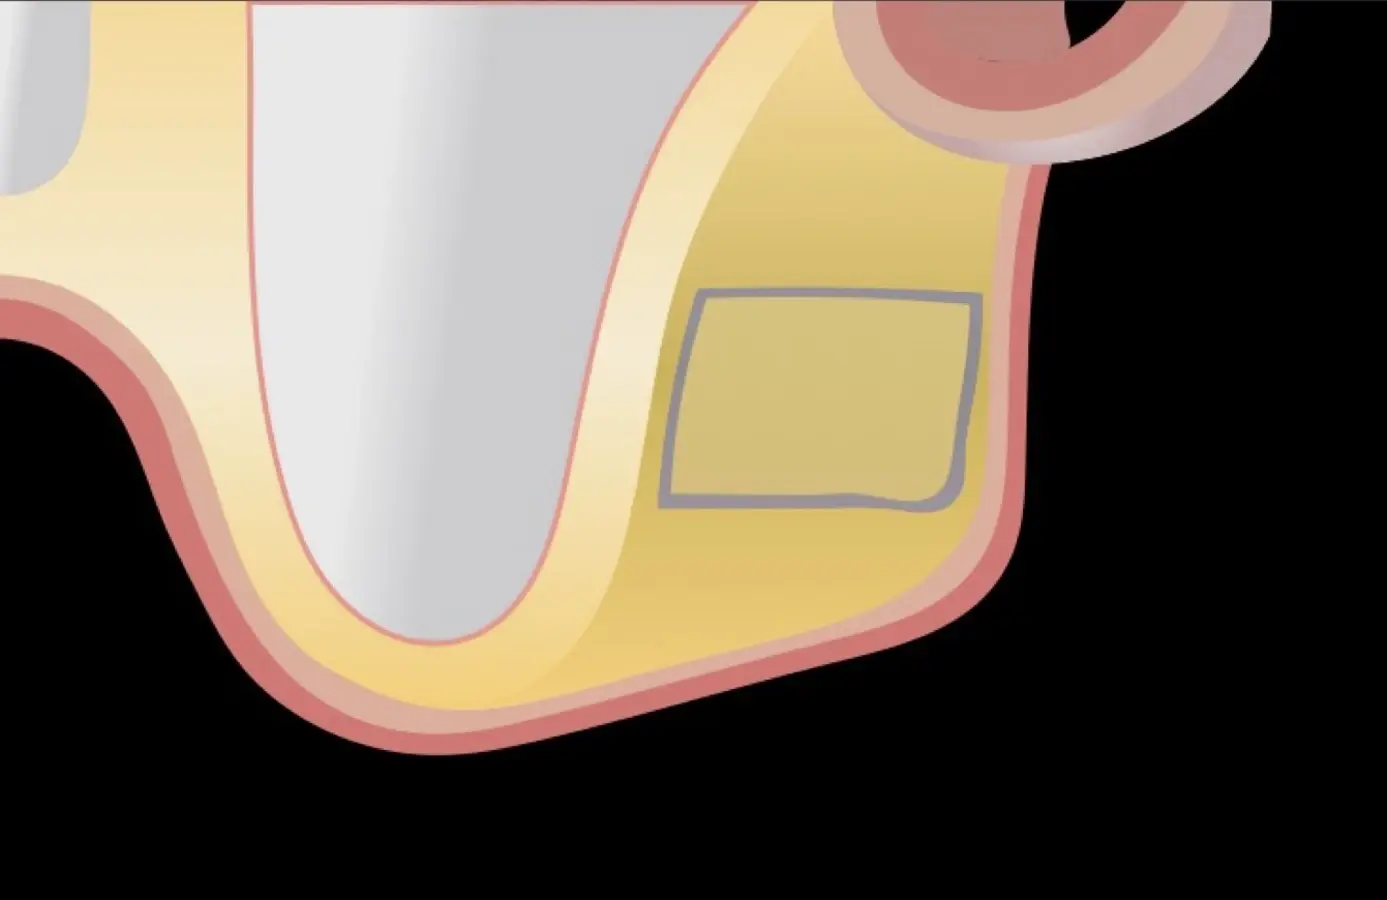

El tipo de inserto a ser utilizado dependerá del espesor de la pared ósea. Si la pared es menor a 0.5 mm, es mejor utilizar insertos de desgaste para prevenir la ruptura de la membrana de Schneider; si el espesor es mayor a 0.5 mm, se puede utilizar insertos de corte de espesor medio (Figura 3).